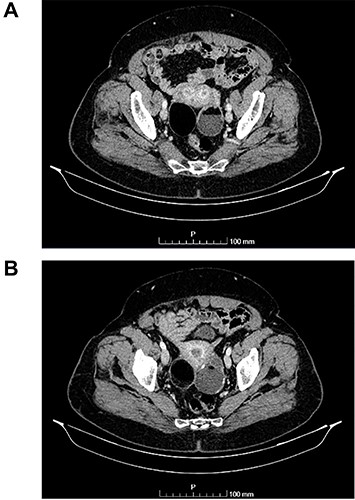

(A and B) Axial images of CT scan showing in the right ovary, a solid mass with predominantly fat density of 55 mm; and in the left ovary, a predominantly cystic mass of 65 mm.

The authors report the case of an asymptomatic 76-year-old female patient, referred to our Gynaecologic Clinic, due to suspicious adnexal lesions on a pelvic ultrasound (US). Menopause occurred at age 53. She had no history of abnormal uterine haemorrhage. Her menstrual cycles had been regular. She had had three gestations: two late abortions and one normal delivery, after which she breastfed. At our clinic, upon examination, vulva, vagina and cervix had no apparent lesions. The vaginal US revealed a right adnexal avascular cystic lesion of 65 mm, a left adnexal hyperechogenic cystic lesion of 60 mm, a normal sized uterus, a diffusely heterogeneous myometrium, an endometrial thickness of 8 mm and heterogenous intracavitary liquid. Her risk of ovarian malignancy assessment (ROMA) score was 28.1%, for a cut-off of 25.3%. Cancer antigen (CA) 125 and Human epididymis protein 4 (HE4) were 25.9 and 98.2, respectively. Lactate dehydrogenase (LDH), alpha fetoprotein (AFP) and beta human chorionic gonadotropin (bHCG) were normal. She subsequently had a magnetic resonance (MR) done (Fig. 1), which suggested bilateral ovarian teratoma. She also had an upper digestive endoscopy and a hysteroscopy that were normal and a computed tomography (CT) done (Figs 2–4) that showed: in the right adnexal region, a solid well-demarcated tumoural mass of 55 mm, with predominantly fat density, peripherical calcifications and a central hyperdense image (similar to a tooth), suggestive of a teratoma; in the left adnexal region, a predominantly cystic bilobated tumoural mass of 65 mm, with peripherical calcifications and an area of fat density, also suggestive of teratoma; and no additional disease. This case was presented at our Multidisciplinary Tumour Board, where surgery was proposed. Thus, she underwent exploratory laparotomy, peritoneal washing, total hysterectomy and bilateral adnexectomy, which ran uneventfully. Intra-operative frozen section excluded ovarian malignancy. She had an uneventful recovery and was discharged home on the third post-operative day. The pathological report revealed bilateral mature cystic teratoma with representation of the three germinative layers and thyroid parenchymal tissue (struma ovarii) (Fig. 5). Both ovaries were atrophic and had a cavitated lesion covered by respiratory epithelium with hyaline cartilaginous, adipose, smooth muscular and mucosa-associated lymphoid tissues (positivity for CD3 and CD20), seromucinous glands and thyroid follicles (homogenous positivity for thyroglobulin). Thyroid follicles were well differentiated, without features of malignancy. Fallopian tubes were normal. There were also uterine leiomyomas and a mucosal endocervical polyp. She was euthyroid and had a thyroid US done, which was normal. Follow-up at first post-operative month, remaining asymptomatic.